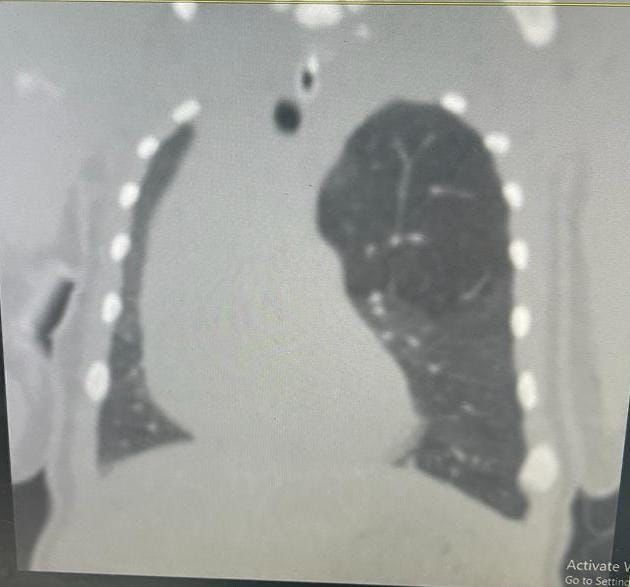

إستقبل مجمع الملك فيصل الطبي بالطائف حالة طفل خديج حديث الولادة يعاني من صعوبة في التنفس، وتم بشكلٍ عاجل عمل فحوصات وتحاليل وأشعة دقيقة للطفل أثبتت وجود تمدد بالفص الأيسر العلوي من الرئة،

وتم تشكيل فريق طبي من عدة تخصصات شملت أطباء جراحة الصدر، وأطباء الرعاية الفائقة للأطفال الخُدج بالمجمع، وبعد دراسة الحالة تم اتخاذ قرار بإجراء جراحة عاجلة ودقيقة لاستئصال الفص الأيسر العلوي من الرئة عن طريق شق صدري محدود بمشاركة الدكتور نادر البرعي استشاري جراحة الصدر، والدكتور جاسر علي استشاري جراحة الصدر، والدكتورة عبير أحمد عبد السلام حسن طبيبة حديثي الولادة.